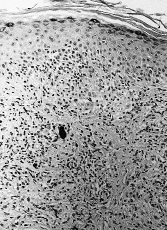

La histología (Figs. 4, 5, 6 y 7) correspondía a un patrón liquenoide en tres de ellos, a una dermatitis espongiótica en otro y una hiperplasia pseudoepiteliomatosa en el restante (tabla II). Realizadas las pruebas epicutáneas, a las pacientes 1 y 2 con la batería estándar del GEIDC, batería de colorantes textiles, mercurio, cadmio y la tinta que ellas aportaron, y al 4 únicamente con su tinta, encontramos una positividad a la tinta la paciente número 2 (++/+++). Hemos realizado 25 controles con dicha tinta, encontrando sólo una positividad, por lo que interpretamos que la reacción de nuestra paciente no es irritativa.

FIG. 4.--Imagen correspondiente a la biopsia tomada a la paciente número 1. Se observa un infiltrado inflamatorio superficial y profundo muy denso en la zona del pigmento rojo.